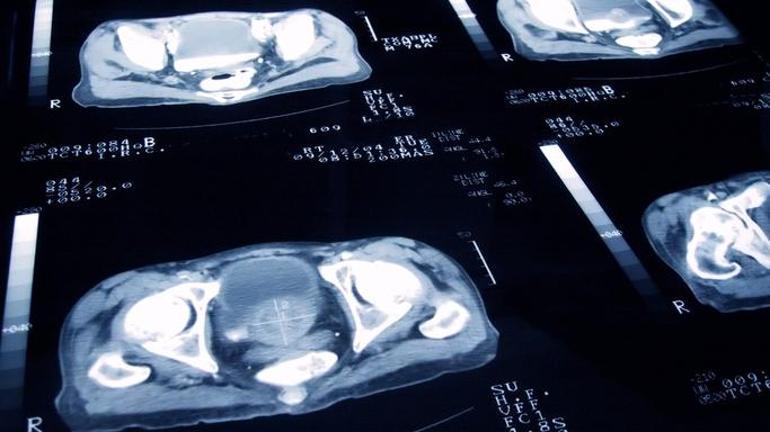

Erkeklerde en yaygın kanser türü olan prostat kanserinde erken tanı artık çok daha mümkün olmuştur. Yakın zamanda geliştirilen teşhis yöntemleri sayesinde, hastalık semptomların ortaya çıkması olmadan teşhis edilebilir. Bu, işleme sürecindeki başarı oranını arttırır. Sinsi olan prostat kanseri, herhangi bir semptom olmadan uzun süre gelişebilir. Bununla birlikte, gelişmekte olan MR teknolojisi sayesinde, tümör daha önce fark edilebilir.

“Prostat kanseri çok sinsi bir hastalıktır, çünkü ilerleme sırasında herhangi bir semptom sağlamaz. Bununla birlikte, ayrıntılı görüntüleme sağlayan MR teknolojileri sayesinde, şimdi prostat kanserini daha net görebiliriz, ilk aşamayı teşhis edebiliriz. Bu, tedaviye daha önce başlamamıza izin verir.

Geçmişte, şüpheli bir durum olduğunda rastgele alanlardan örnekler alıyorduk. Yürüyüş alanını bir turuncu bulma girişimi olarak düşünebiliriz. Bununla birlikte, manyetik rezonans görüntüleme sayesinde, şüpheli bölge doğrudan tespit edilir ve sadece o bölgede biyopsi ile teşhis edilir.